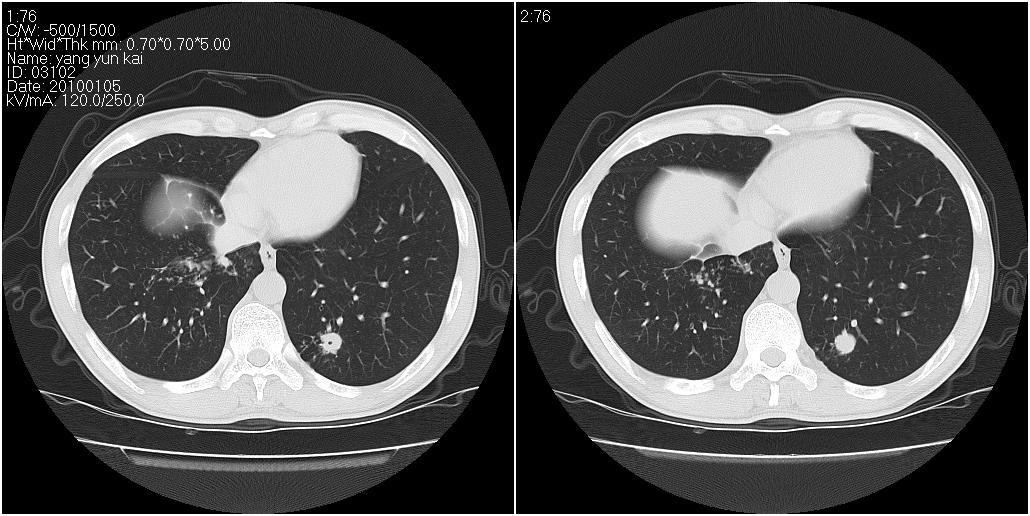

标题: CT23980:男性,47岁。近来咳痰、咳血,血沉增快(40左右),

男性,47岁。近来咳痰、咳血,血沉增快(40左右),痰中未检出结核杆菌。

两肺继发性肺结核并多发性结核球形成,部分病灶内空洞形成。